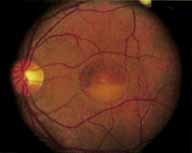

Ancillary Tests

Fluorescein angiography demonstrates increased transmission of choroidal fluorescence in the macula during early phases of the study, without late leakage of dye or fluorescein staining. In addition, an annular pattern of hyperfluorescence is often seen in the macula, highlighting the bull's-eye pattern seen on fundus examination (Fig. 4). Visual field defects include central scotoma, peripheral field loss, and ring scotoma.

|